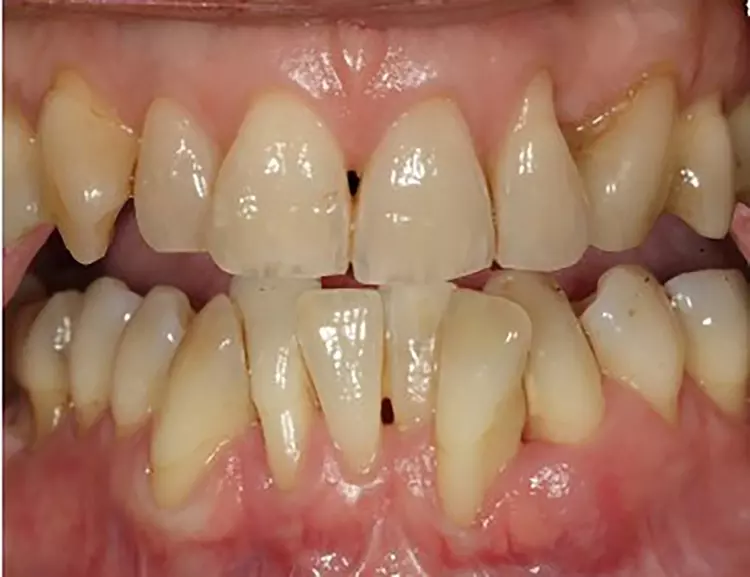

Der extraorale Befund war unauffällig. Der intraorale Befund (Abb. 2) zeigte eine lückenlose Dentition und eine verbesserungsbedürftige Mundhygiene (PI: 37%, BI: 2%) auf. Die Zähne 14 und 23 fehlten aufgrund einer Nichtanlage.

Einige Zähne waren konservierend suffizient versorgt (Abb. 3). In der Unterkieferfront bestand ein ausgeprägter Engstand mit Verschachtelung (Crowding).

Im Seitenzahnbereich bestanden an zahlreichen Zähnen Furkationsbeteiligungen. Die Zahnbeweglichkeit war an 2 Zähnen deutlich erhöht. An mehreren Zähnen lagen zudem gingivale Rezessionen vor.